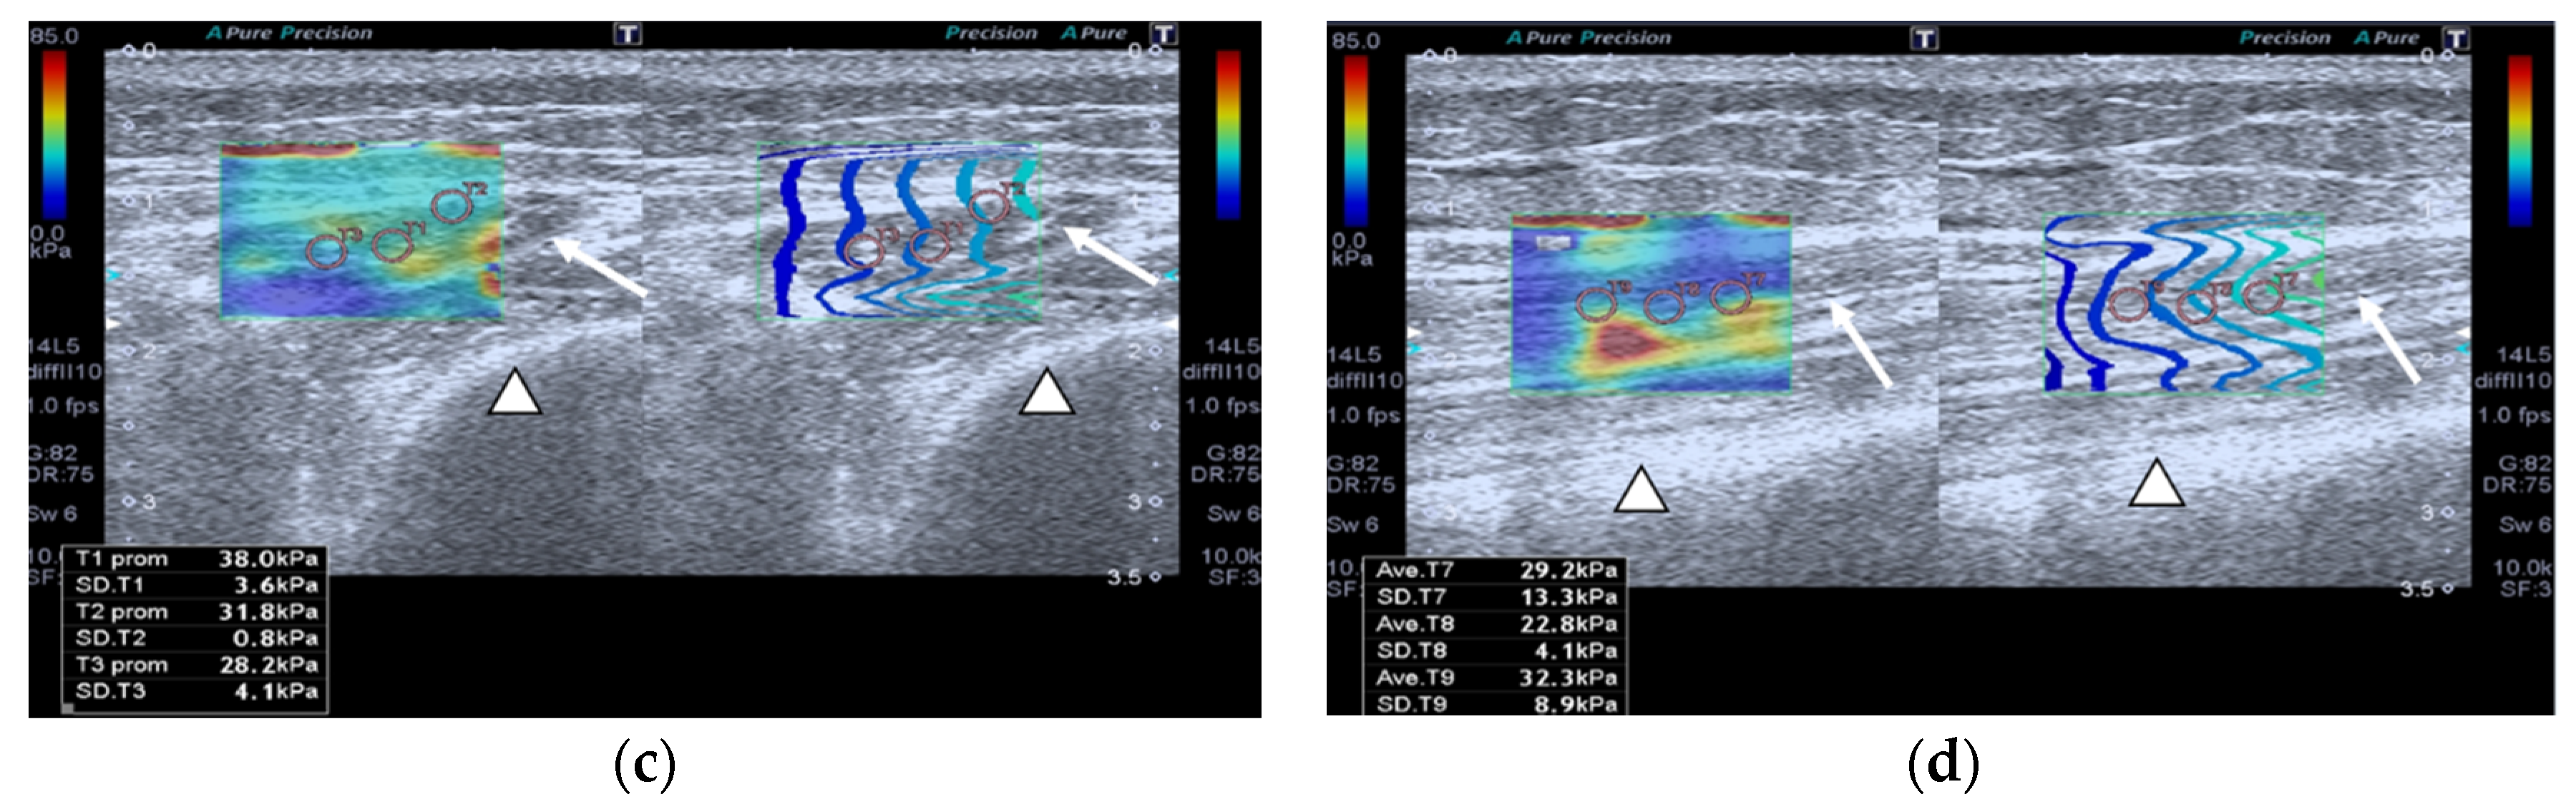

Figure 4.

Transversal QRF muscle of a patient with multiorgan failure (77 years old). (a). Transversal ultrasonography scan shows the QRF muscle (arrow) and vascularization after contrast-enhanced ultrasound (CEUS) administration (arrowhead). CEUS imaging and time–intensity curve analysis are shown using the built-in software. (b) ROI (pink circle) in the area of strongest enhancement indicates maximum perfusion in the QRF. (c) ROI (pink circle) in the area of lowest enhancement indicates minimum perfusion in the QRF.

Images of the peak maximum and minimum CEUS intensity of a patient and a healthy control are shown in Figure 3 and Figure 4.